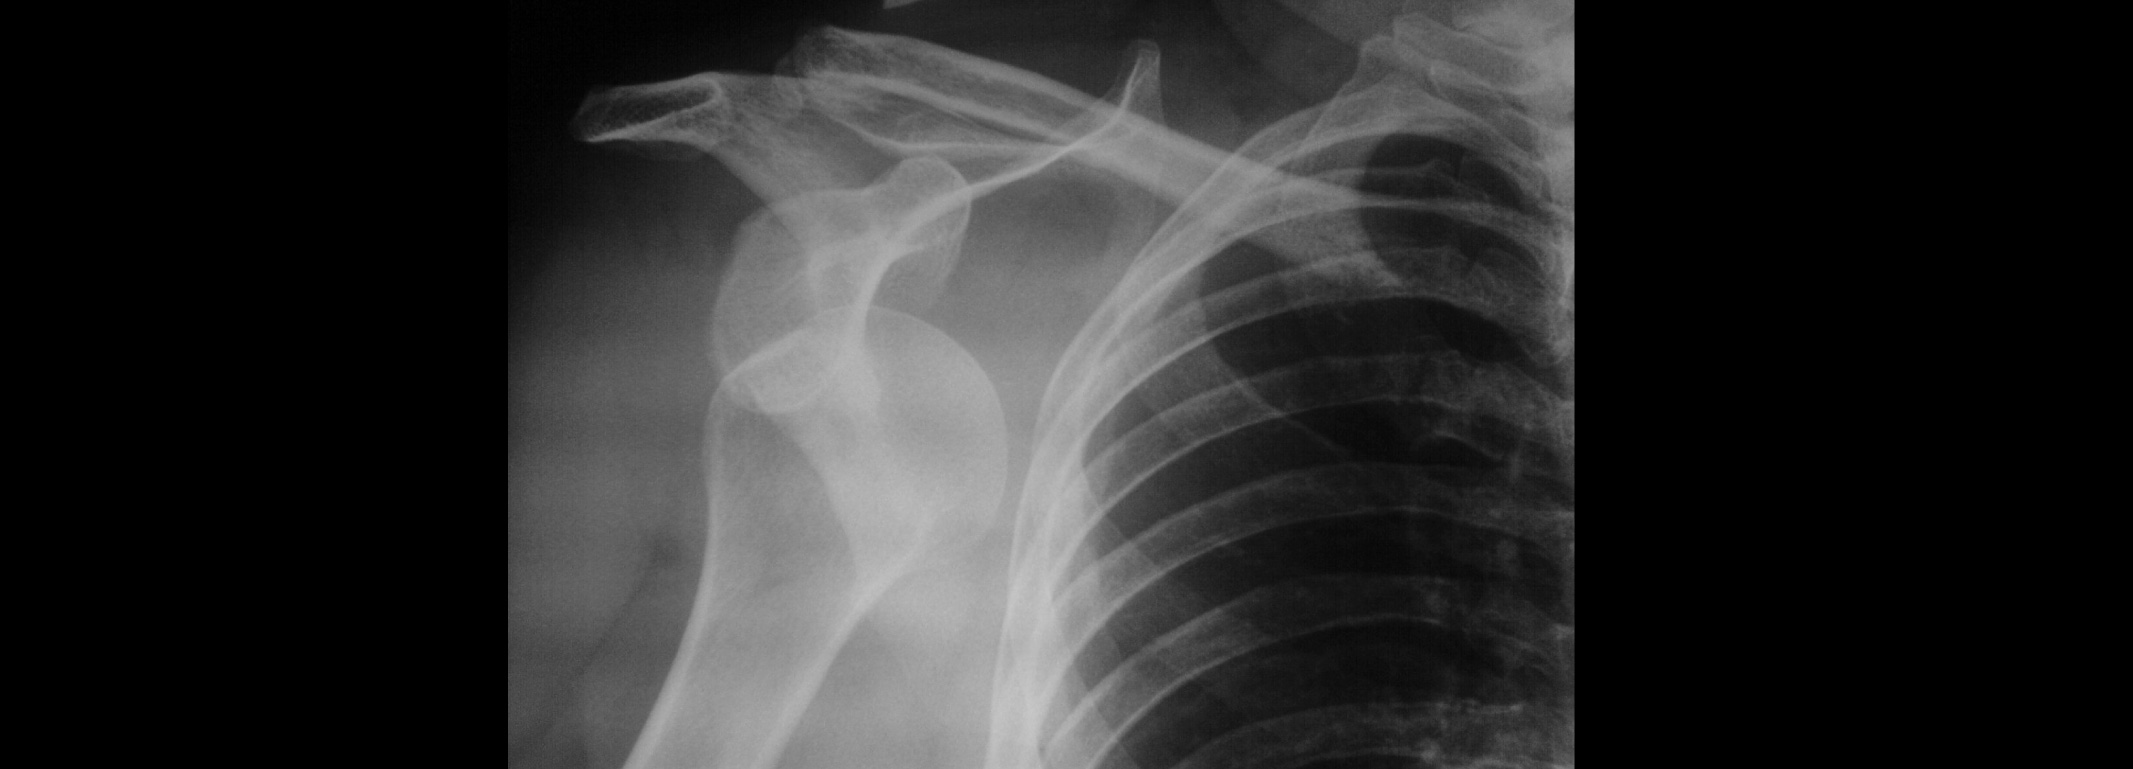

El hombro es la articulación con mayor rango de movimiento del cuerpo humano; sin embargo, su estabilidad y posicionamiento funcional dependen del alto porcentaje de ligamentos y tejidos blandos que lo rodean, por lo que se encuentra susceptible a lesiones. Cuando ocurre una dislocación de hombro, la cabeza humeral se sale de la glenoides, destruyendo o rasgando el elemento estabilizador. Este problema también se conoce como luxación de hombro, inestabilidad del hombro o inestabilidad glenohumeral.

La causa más frecuente de la dislocación de hombro es un traumatismo directo o indirecto en la articulación, que provoca que la cabeza del húmero se salga de la glenoides. Esto daña las estructuras que normalmente estabilizan el hombro: los ligamentos y las cápsulas articulares.